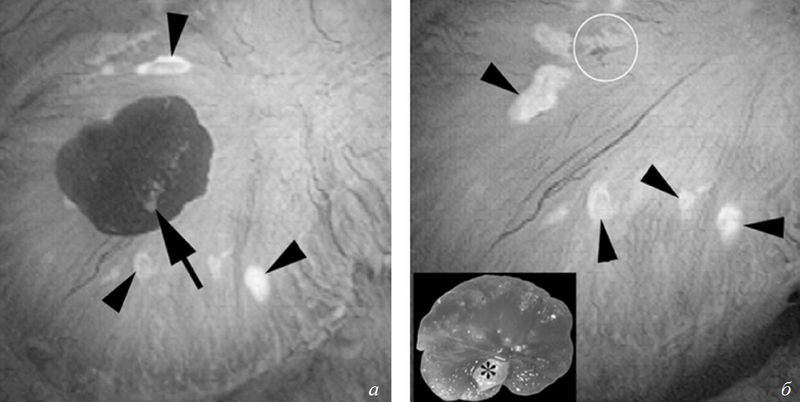

Во время эндоскопического удаления камня почки достаточно часто можно видеть камни, растущие на бляшках в области сосочков чашечек (рис. 1).

На фоне всех пациентов с мочекаменной болезнью явно выделяется фенотип больных, у которых формирование кальцийоксалатных конкрементов происходит без каких-либо системных заболеваний, способных прямо влиять на их возникновение; такие больные определены в группу с идиопатическим кальцийоксалатным нефролитиазом [5, 6]. У большинства из них можно проследить семейный и/или генетический характер наследования идиопатической гиперкальциурии. При этом кальцийоксалатные конкременты у этой группы пациентов образуются в основном на бляшках (см. рис. 1).

Рис. 1. Прикрепленные к бляшкам Рэндалла конкременты у идиопатических кальцийоксалатных (CaOx) камнеобразователей: а) эндоскопический вид камня CaOx, прикрепленного к верхушке почечного сосочка (на снимке отмечено стрелкой). Бляшки Рэндалла вокруг прикрепленных конкрементов (треугольники); б ) сосочек после удаления камня. На вставке видна папиллярная поверхность того же камня. Небольшой участок белесоватого материала на камне — гидроксиапатит, при этом сам камень на сто процентов кальцийоксалатный (отмечено звездочкой)